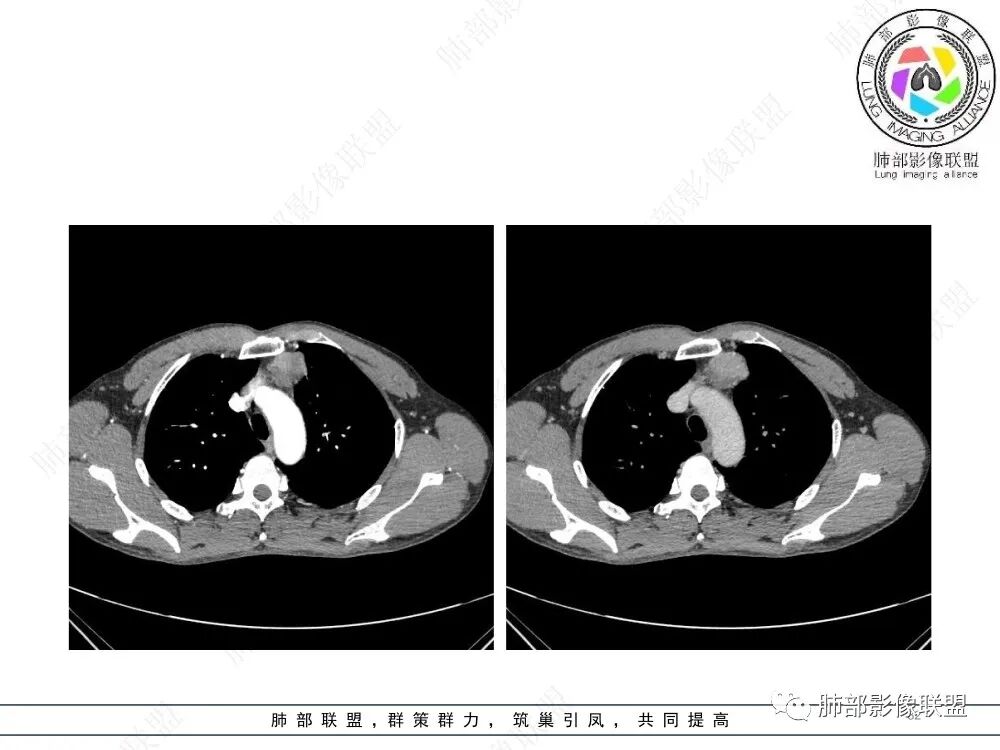

流心明智:男,47,咳嗽、咳痰1年余。胸部CT:前纵膈偏左类圆形肿块,瘤肺界面清晰光整,纵隔侧部分层面絮状影?平扫密度较均匀,增强后轻度强化,内可见宽带及线样低密度分隔。邻近左上肺受压凹陷。考虑胸腺肿瘤,AB型?胸腺Ca?鉴别淋巴瘤、N源性肿瘤、CD等。

南边:支持前纵隔、胸腺瘤首选,晨读其实定位上还是有点难度,定性常规还是考虑胸腺瘤,其他的几率比较低一些,需要鉴别的是胸膜SFT,神经源性,可惜的是没重建,一直在犹豫胸膜来源的可能性。

2、影像特点:前纵隔偏左侧软组织影,密度相对均匀,未见明显包膜钙化及实质内钙化,局部边缘浅分叶,周围脂肪间隙密度增高、浑浊,未见侵犯大血管、未见纵隔内淋巴结转移、未见侵犯心包内结构、未见胸膜转移结节、未见肿块沿着纵隔胸膜蔓延,未见胸腔积液。增强后动脉期不均匀强化,未见明显纤维分隔。

3、 病 例 小 结:40岁以上,前纵隔偏侧性生长的肿块,常规考虑胸腺瘤。难点就在于胸腺瘤的分型。但是对于前纵隔占位影像诊断的关键在于区分胸腺囊肿、胸腺瘤、胸腺癌及其他恶性肿瘤。至于胸腺瘤,主要在于判断有无侵袭性。